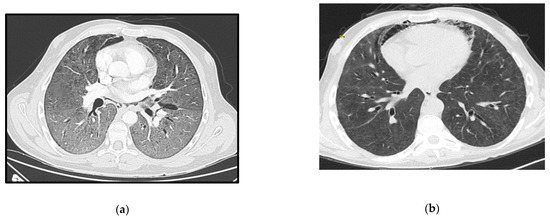

A 53-year-old woman, with no relevant medical history so far, was brought to the ER due to a two-month history of progressive psychomotor slowness and confusion, which had worsened in the week before. At physical examination, she was agitated and febrile. Head CT scan showed some intra-axial lesions in the left frontal and temporal lobes. The cerebral spinal fluid (CSF) had mild pleocytosis and moderately elevated proteins. The serology for HIV was positive, and the nucleic acid test of the CSF was positive for toxoplasma gondii. She was admitted in the ICU with a de novo diagnosis of HIV infection, with severe immunosuppression (CD4+ count 28 cells/mm3), clinically manifested as cerebral toxoplasmosis. On day 3, she began coughing, with respiratory hypoxemic insufficiency and bilateral diffuse glass opacities on chest-CT scan (Figure 3a). The presumptive diagnosis of PJP was posteriorly confirmed with both direct dye-examination and PCR positive for P. jirovecii in BAL. She was treated with TMP-SMX for both PJP and cerebral toxoplasmosis. Following one week of appropriate medical treatment, the patient had a favorable response, and was discharged to the ward for further care.

Persistent fever and elevated inflammatory markers ensued, with isolation of multidrug-resistant Pseudomonas aeruginosa in respiratory secretions. Chest X-ray confirmed lobar nosocomial pneumonia. She started a targeted antibiotic course with cefepime, with good clinical, analytical, and radiological response. Roughly one week later, she was extubated to non-mechanical ventilation, and rapidly weaned off respiratory support to no oxygen supplementation. The evolution in her condition can be seen at the images in Figure 3b.

Figure 3. Case 3 thoracic CT-scan at diagnosis (a) and follow-up (b).